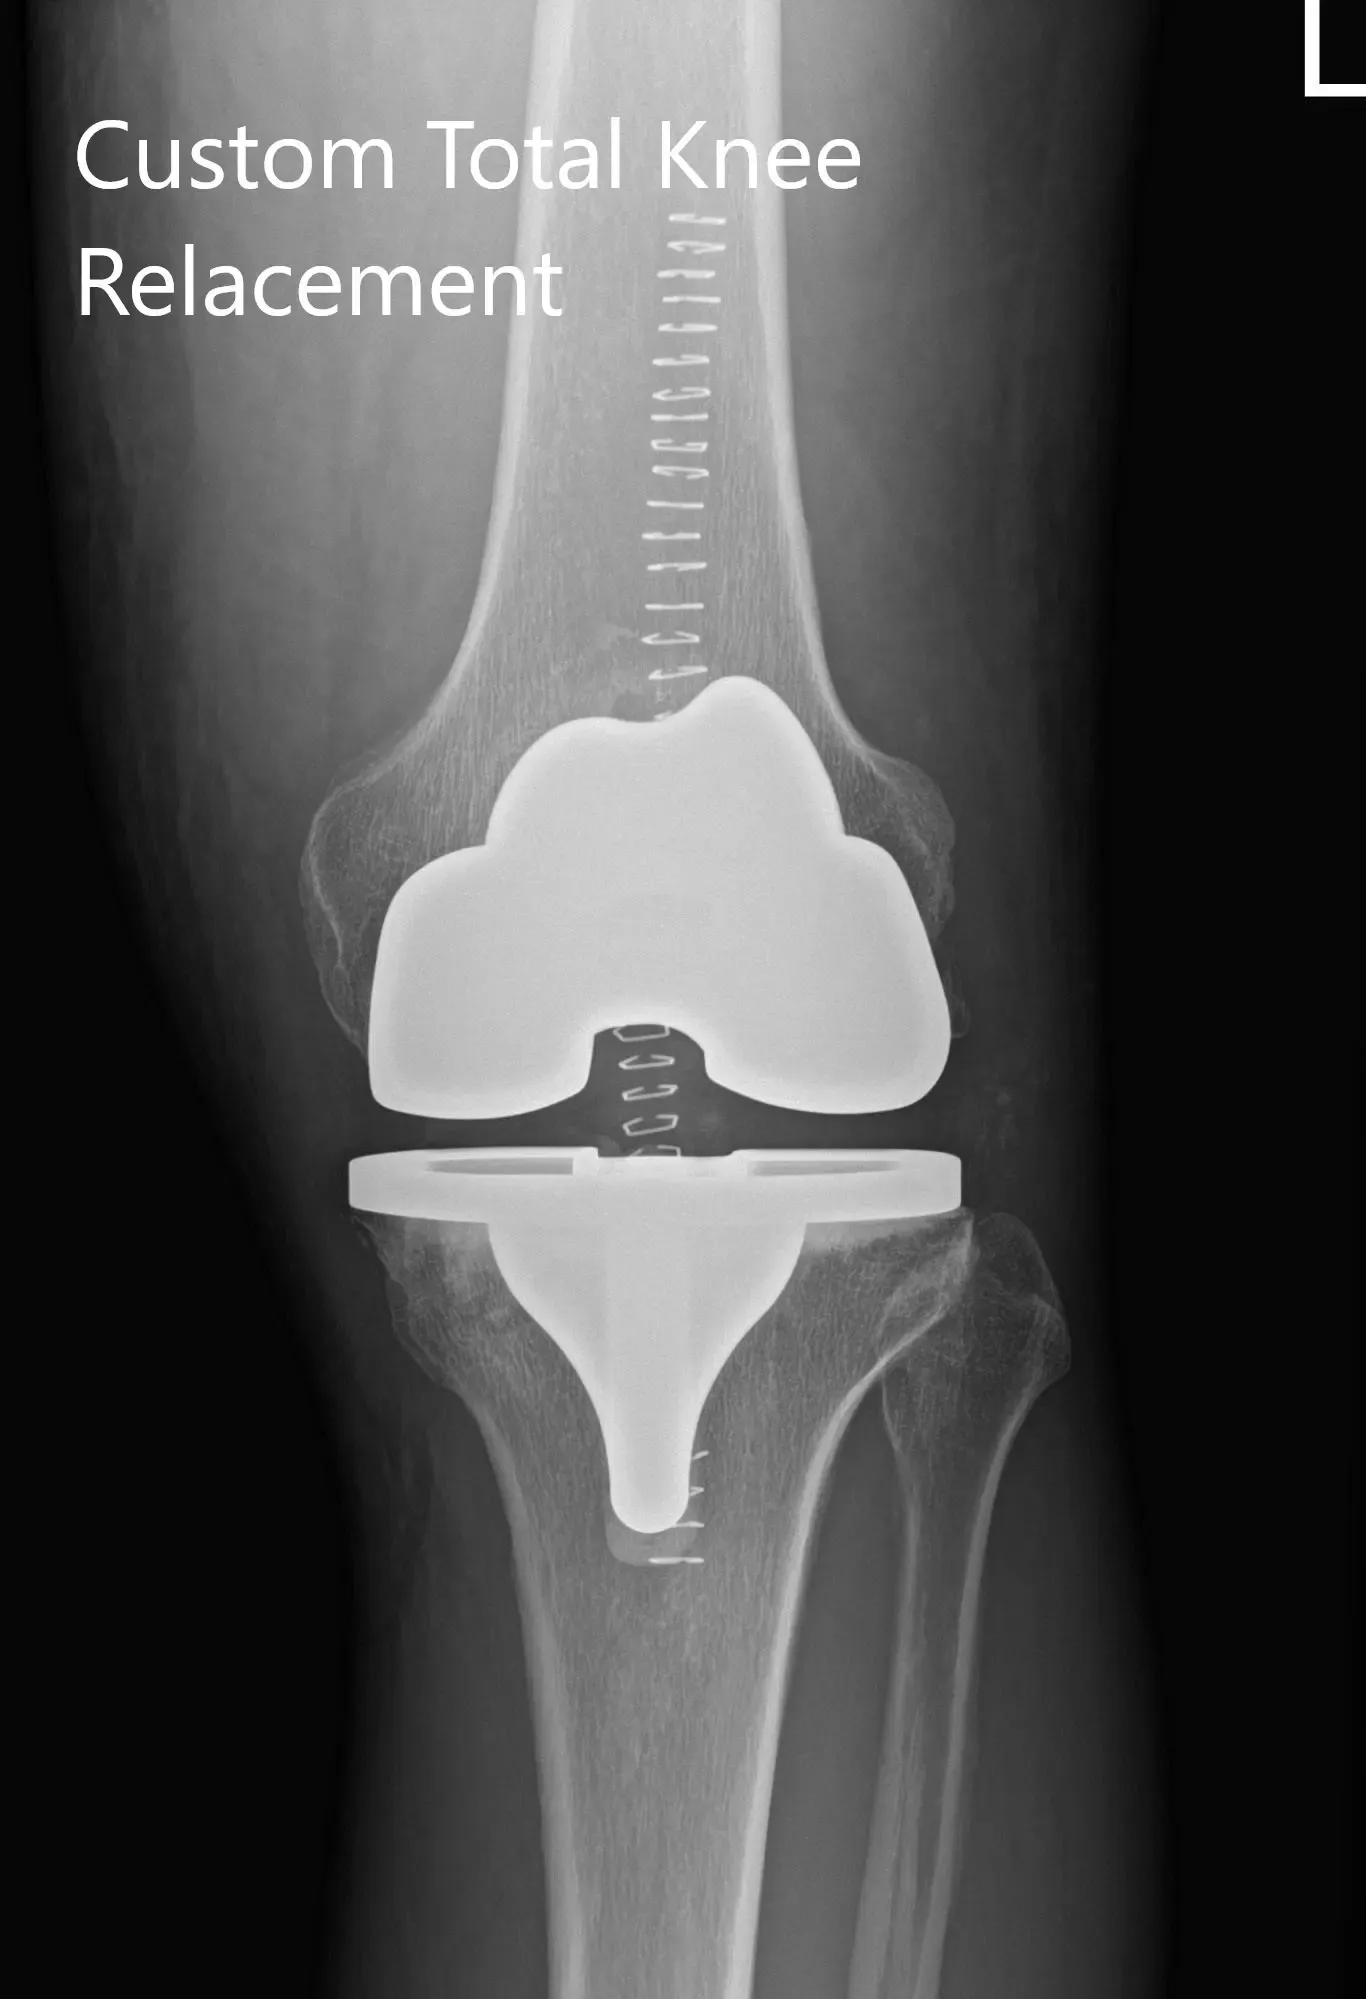

The patient had a preoperative CT scan for assessing his biomechanics and anatomy to aid in bone preserving surgery. The images were used to construct custom patient-specific implants and instruments. Unique 3D printed cutting blocks are used to preserve maximum bone. Preoperative plans are created using the 3D images to ensure correct alignment and prevent implant mismatch which is common with traditional implants.

Complete Orthopedics patient-specific surgical plan for a left custom knee replacement in a 70-year-old female.

Complete Orthopedics patient-specific surgical plan for a left custom knee replacement in a 70-year-old female (scan 2)

Implant – Custom femur with a custom tibia and patella with 8-mm polyethylene insert.